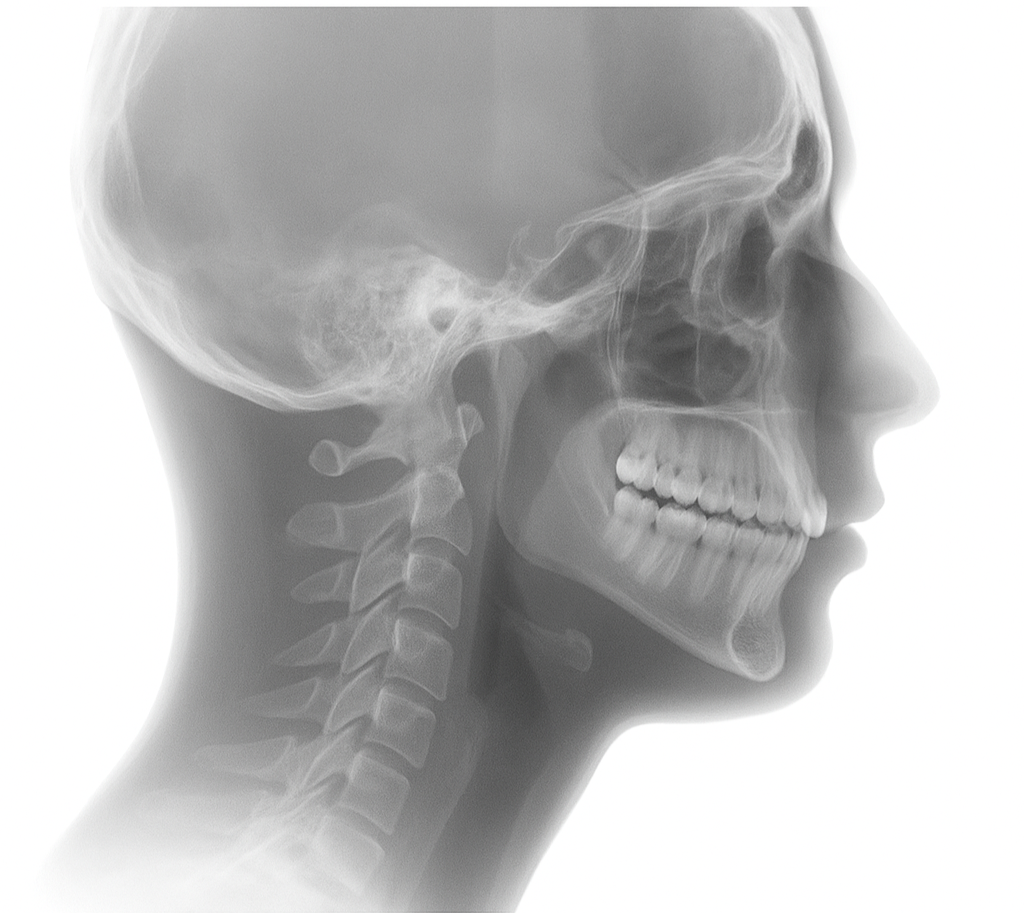

The Panoramic OP 3D LX is an advanced dental imaging system designed to provide a complete, high-resolution view of your entire mouth in a single image. This technology captures your teeth, jawbones, and surrounding structures with remarkable clarity, helping dentists identify issues such as cavities, infections, bone loss, and impacted teeth. Its quick, comfortable process makes it an excellent tool for routine check-ups, pre-treatment evaluations, and surgical planning. The OP 3D LX minimizes patient radiation exposure while maximizing diagnostic accuracy, ensuring a safe and effective experience for every patient.